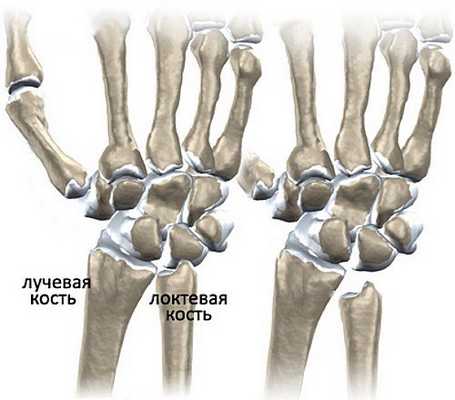

Клинически значимая анатомия

Проксимальный запястный ряд срединно-запястного сустава в значительной степени отвечает за движение запястья, в отличие от относительно фиксированного дистального запястного ряда. Полулунная кость является центральной костью в проксимальном ряду, и она сочленяется с ладьевидной, головчатой, трехгранной, а иногда и крючковидной костью. Более проксимально, полулунная кость является компонентом лучезапястного сустава, и она также сочленяется с локтевой костью через треугольный фиброхрящевой комплекс (ТФХК). Следует отметить, что почти 10 % аксиально-лучевой/локтевой/кистевой нагрузки передается через ТФХК и впоследствии на локтевую кость, а 35 % - через лучеполулунное сочленение [1].

Слева - нормальная длина лучевой и локтевой костей, справа - врожденная короткая локтевая кость.

Длина двух костей предплечья, локтевой кости и лучевой кости, обычно не одинакова. Мы можем разделить длину между дистальными суставными поверхностями лучевой кости и локтевой кости, называемую лучелоктевым индексом. Он может быть отрицательным, положительным или нейтральным. Отрицательный лучелоктевой индекс указывает на то, что дистальная суставная поверхность локтевой кости расположена более проксимально, чем лучевой кости, положительный лучелоктевой индекс указывает на стадию, когда дистальная суставная поверхность локтевой кости расположена более дистально по сравнению с поверхностью лучевой кости, и, наконец, нейтральный лучелоктевой индекс означает, что локтевая и лучевая поверхности находятся на одном уровне [5].

Существует значительная связь между отрицательным лучелоктевым индексом и болезнью Кинбека. Лучелоктевой индекс относится к непропорционально укороченной локтевой кости по сравнению с лучевой [1].

Изображение 2: Взаимосвязь между радиальной длиной и лучелоктевым индексом. Радиальная длина - это мера от дистального конца локтевой кости до лучевого шиловидного отростка. Когда лучелоктевой индекс нейтрален, радиальная длина должна составлять от 9 до 12 мм.